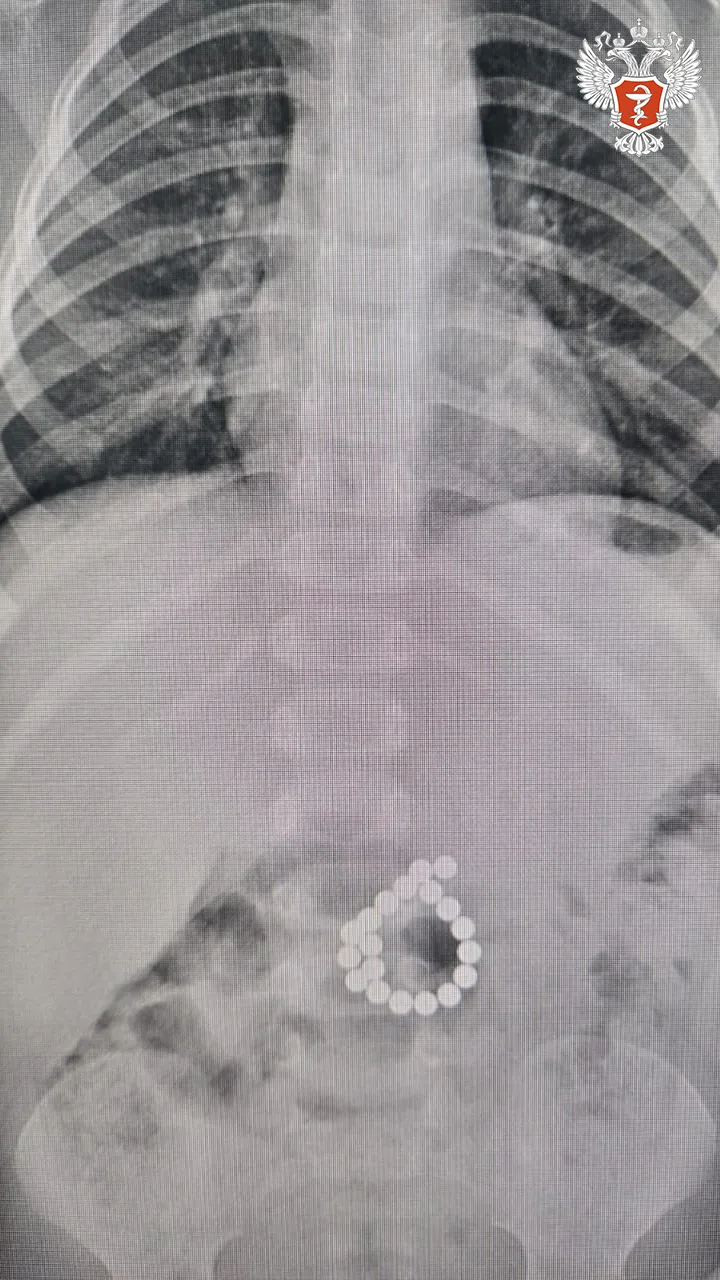

🤩 Краснодарские хирурги удалили опухоль весом 13 кг

Мужчина поступил в Краевую клиническую больницу № 2 с болями, которые на протяжении долгого времени его беспокоили, однако визит к врачу откладывал.

↪️ В ходе обследования врачи выявили опухоль, которая занимала практически всю брюшную полость. Диаметр новообразования достигал 50 см, а вес – 13 кг.

Специалисты приняли решение о проведении операции. Врачи удалили пациенту опухоль брюшной полости и выполнили пластику почечных сосудов, что позволило сохранить почку.

❤️ Сейчас пациент чувствует себя хорошо и находится под наблюдением врачей.